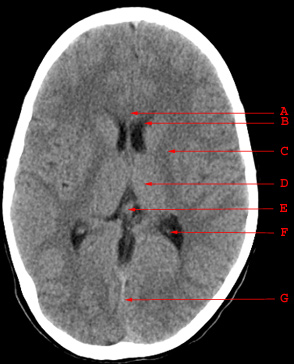

A. Genu of the Corpus Callosum B. Anterior Horn of the Lateral Ventricle C. Internal Capsule D. Thalamus E. Pineal Gland F. Choroid Plexus G. Straight Sinus